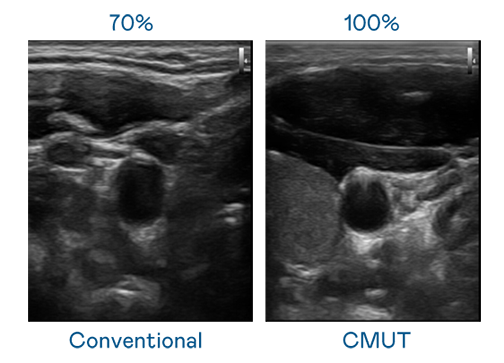

CMUT 技术是一种用电容式微机电元件来产生超音波讯号的技术。与传统 PZT 压电式技术相比,CMUT 频宽增加 30%,更宽频的超音波讯号让影像解析度大幅提升,是实现高影像品质医疗超音波扫描、促进精准医疗发展的关键技术。

超音波影像的解析度高低,首先取决于探头能发出的讯号频宽。麻花豆电影高清 CMUT 可提供高清晰的超音波讯号,提供高频宽、高灵敏度、影像纹理细节更高的超音波影像,协助医护人员缩短影像判读时间及利用精准的医疗影像进行诊断。